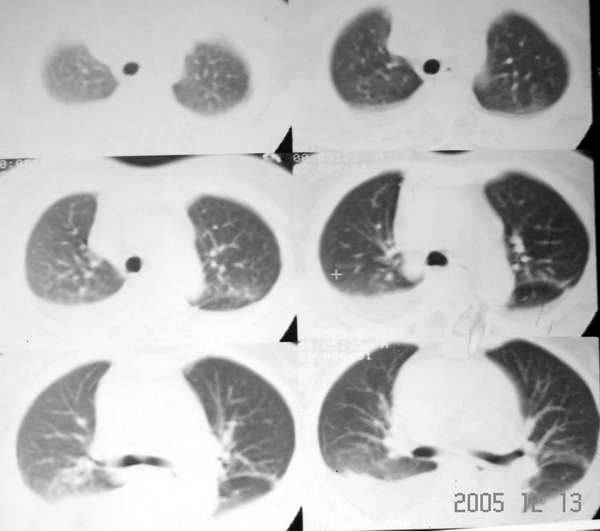

f43y昨日突发胸剧痛,今下午来医院并行ct平扫示:左下肺少许淡薄渗出病灶,双侧胸腔积液以右肺为甚,心包积液。

我认为,一般情况胸腔积液与心包积液并没有相关性,我们经常看到胸腔积液,但心包积液比胸腔积液要少。而这个患者心包积液较重,且发病较急,存在心包填塞的表现,右心房增大,说明回心血流受阻,肺淤血,可能会导致胸腔积液。该患者心包积液较重,建议进一步增强扫描。

心包积液基本可以肯定。两侧胸腔积液,心脏或肾脏病变或血浆蛋白过低都可引起胸腔积液。心包积液常拌有胸腔积液,可为单侧性或双侧性。上海一医大《x线诊断学》把其列为x线表现之一。

心包积液常伴或多或少,单侧或双侧的胸腔积液.

患者急性起病,影象学表现为大量心包积液和双侧胸腔积液,心包积液密度较高,应该考虑为积血,患者没有外伤史,自发性心包积血应该想到主动脉夹层动脉瘤心包内部分破裂的可能,主动脉根部明显增粗也支持该诊断。关于胸腔积液有两种可能的解释,一是由于夹层的压力很高,造成血性胸腔渗出;另外就是由于心包填塞造成腔静脉系统压力增高,引起胸腔的渗出改变。

心包大量积液,双侧行腔积液,升主动脉增宽,结合突然发病,不排除主动脉夹层破裂。

心包及胸腔积液,双下肺血管增粗,以右下肺为著,考虑肺淤血